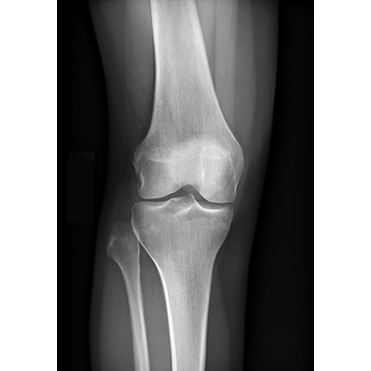

The patient reported acute onset of right lateral knee pain after being slide-tackled during a soccer match five days earlier. She experienced a varus force to her knee as she went for the ball. She reported a sensation of "popping out" at the lateral aspect of her knee at the time of injury. She stated that she had a visible deformity noted to the lateral inferior aspect of her right knee, which was self-resolved by the time she presented to a local ED for initial evaluation. She did not recall exactly how or when it reduced. She was unable to bear weight immediately after the injury. In the ED, radiographs were obtained Case Photo #1 Case Photo #2 Case Photo #3 Case Photo #4 which were negative for acute fracture or dislocation. The patient did not recall the diagnosis, but was recommended a compression wrap, crutches, and analgesics. She was advised to follow up with Sports Medicine. She presented to the Sports Medicine clinic with continued right lateral knee pain with weight-bearing, knee instability, and right anterolateral ankle pain. She reported minimal knee or ankle swelling. She denied symptoms of catching, clicking, locking, skin changes, or lower extremity paresthesias. She had no prior history of injury to the right knee.

Inspection of the right knee revealed mild soft tissue swelling around the proximal fibula, with no deformity or ecchymosis. There was tenderness to palpation at the fibular head, proximal tibiofibular joint, and lateral joint line. She had active range of motion from 0 to 135 degrees, with pain in terminal flexion and extension. Strength was 5/5 with resisted knee extension and 4/5 with resisted knee flexion, limited by pain. On provocative testing, there was lateral knee pain with modified Apley and McMurray tests. Thessaly was not completed due to pain. Additionally, there was pain with varus stress testing, without instability. Lachman, anterior drawer, and posterior drawer tests were deferred due to significant pain and guarding. On neurovascular assessment of the right lower extremity, she had intact sensation to light touch, and skin was warm and well-perfused, with intact pedal pulses.